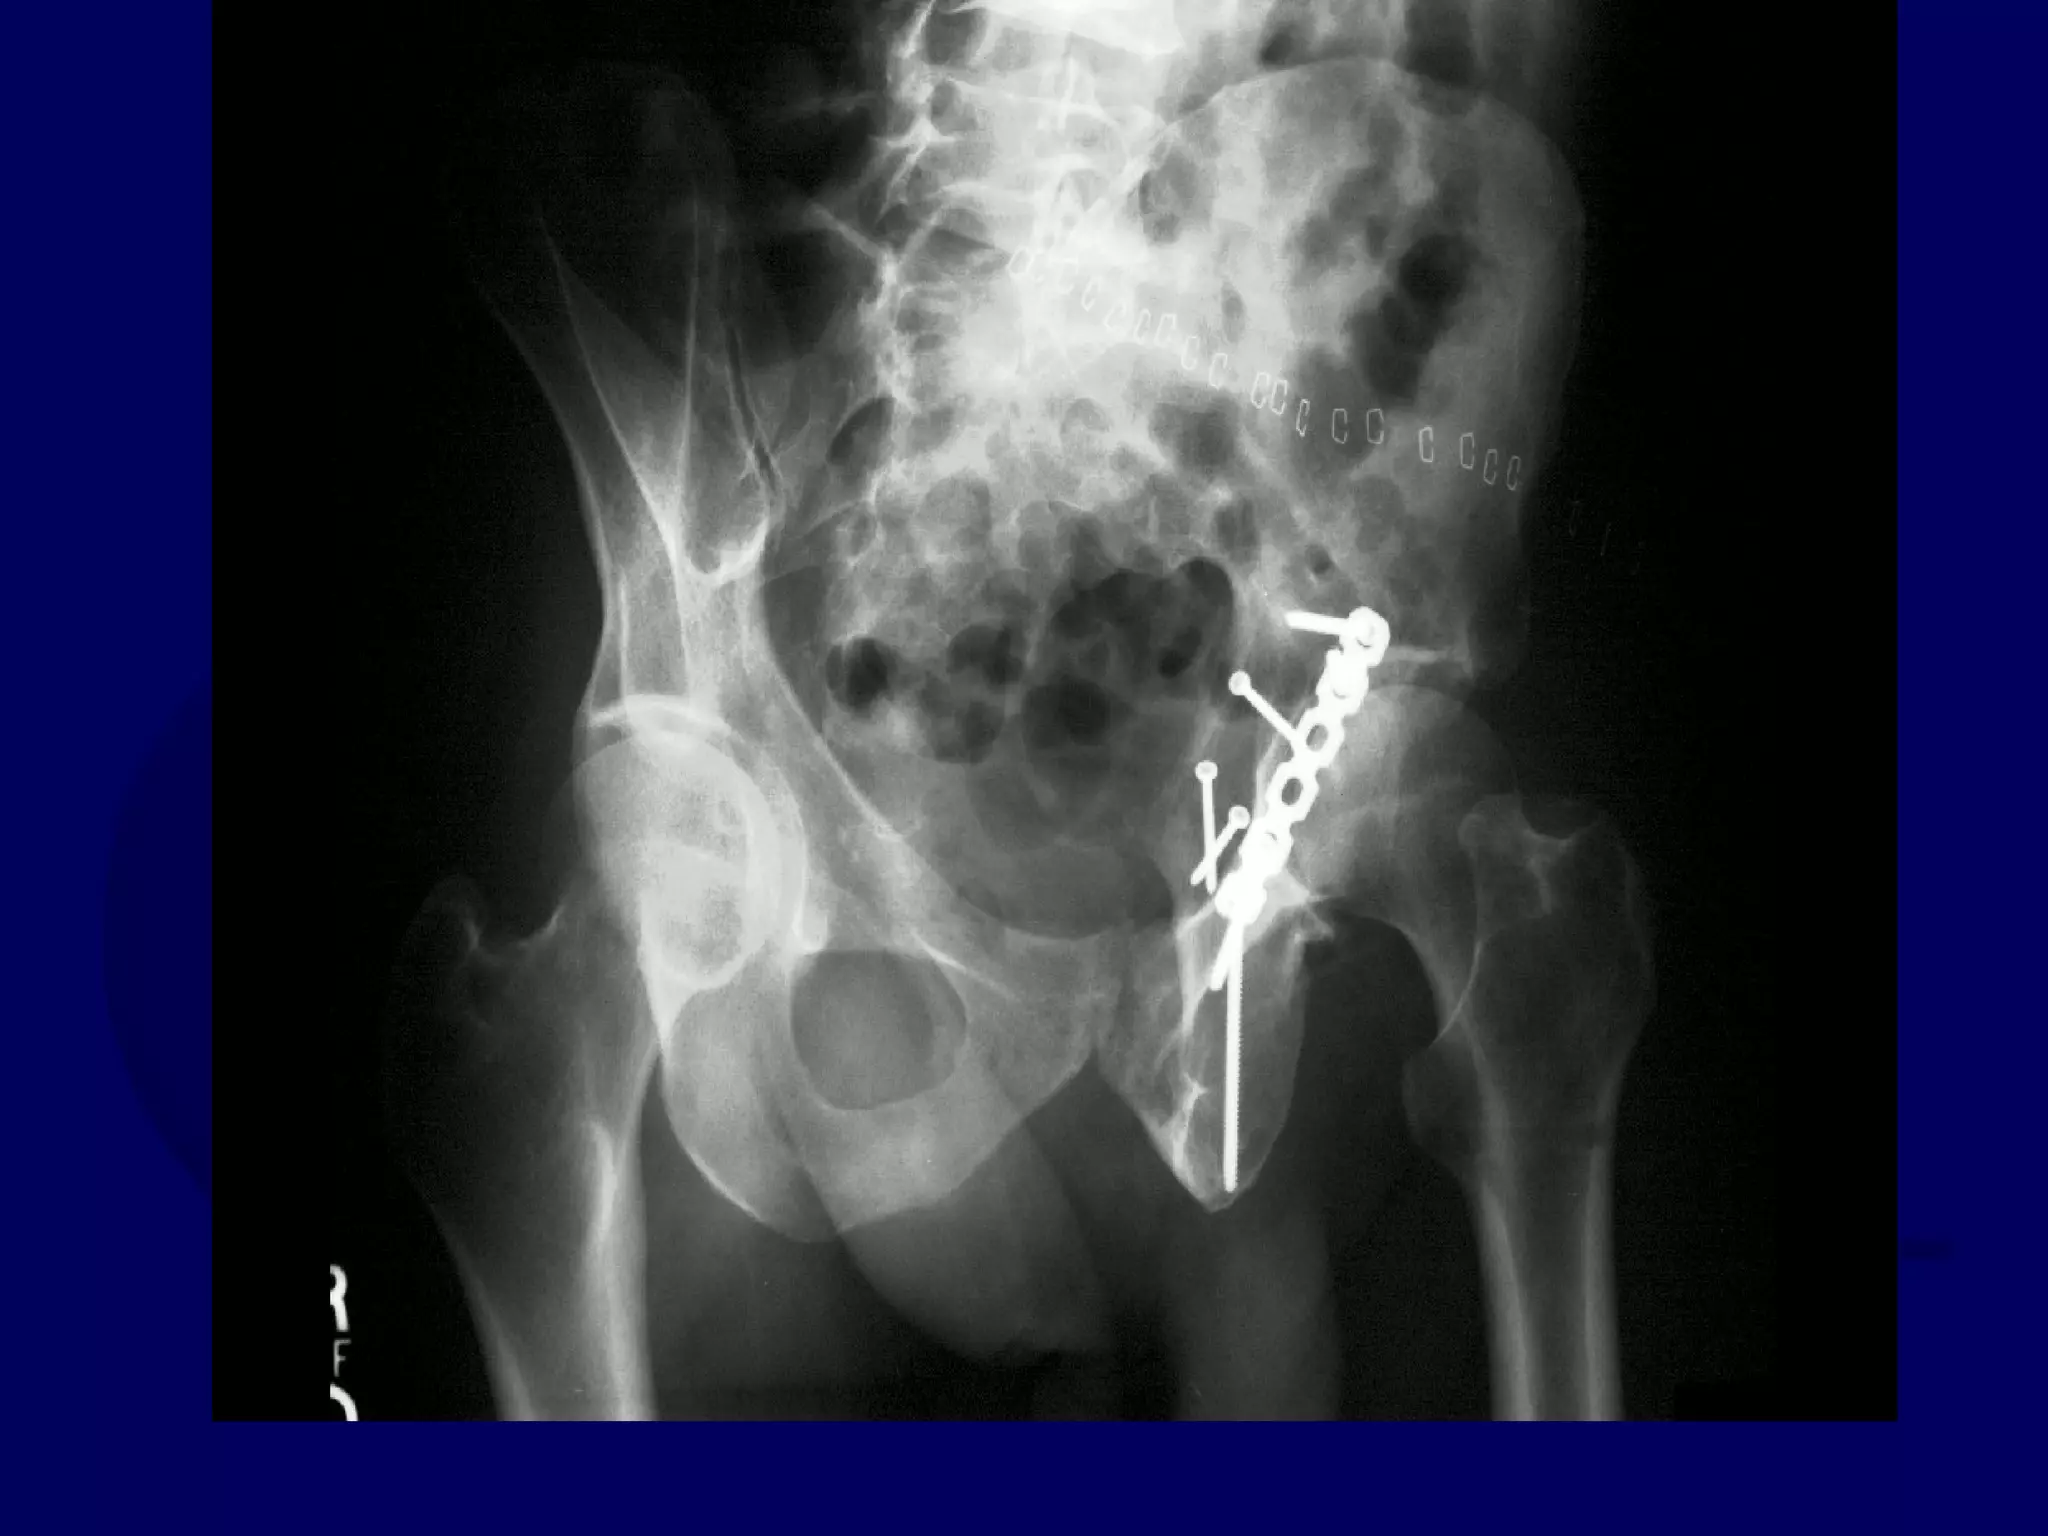

Special Case

“T-Type” Acetabular Fracture

Proximal Femur Fracture

14 y.o. Male

Sequential K-L / Ilioinguinal

Approaches

P.J. 00.12.16

Initial Kocher-Langenbeck

Approach

P.J. 00.12.18

Subsequent Ilioinguinal

P.J. 00.12.22